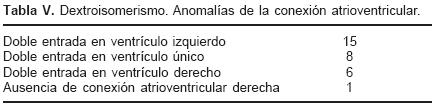

En el grupo mixto el trayecto de los colectores provenientes de cada pulmón dependió de los sitios de conexión anómala (Tabla II). Los setenta y tres corazones en situs solitus e inversas presentaron un defecto septal interatrial de tipo orificio oval (Figs. 2, 4, 7 y 9), mientras que en los treinta corazones con dextroisomerismo existió un atrio común y una bandeleta septal interatrial que separó dos grandes comunicaciones (Fig. 11). Todos los corazones presentaron dilatación de las cámaras derechas, del tronco y ramas de la arteria pulmonar así como hipertrofia del ventrículo derecho (Fig. 12). Respecto a las cámaras izquierdas el atrio fue pequeño e incompleto por carecer del SVP (Fig. 2), el ventrículo izquierdo y la válvula mitral tuvieron características normales. Las cardiopatías asociadas en los setenta y seis corazones con situs solitus e inversus se consignan en la Tabla III. Los treinta corazones con dextroisomerismo presentaron un patrón complejo de asociación de anomalías intracardíacas y vasculares (Tabla IV); en las Tablas V y VI se muestran respectivamente los tipos de conexión atrioventricular y ventriculoarterial en dextroisomerismo.